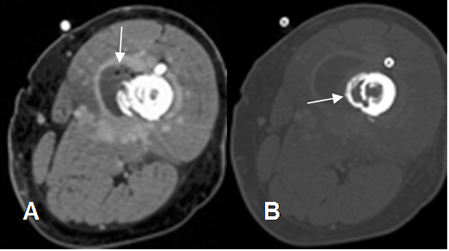

Fig 31 A. Osteomielitis.

A: TAC axial en ventana de tejido. Absceso de tejidos blandos con burbujas de aire y captación de sus paredes, en la parte lateral del muslo.

B: TAC axial en ventana ósea. Destrucción e irregularidad de la cortical, por osteomielitis asociada.